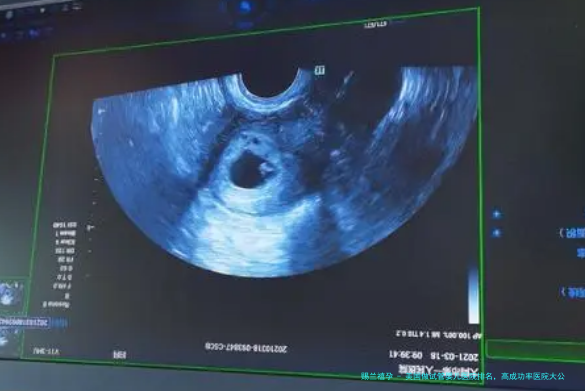

医学技术和配备:领先的医疗技术和配备是保障试管婴儿成功的关键。如第三代试管婴儿技术,能够进行胚胎染色体筛查和诊断,提高胚胎着床率和减少小产风险。医院拥有先进的试验室器械,如胚胎培养箱、显微镜等,也有利于提高胚胎的培养质量。

GenPrime 洛杉矶生育中心(GPLA)构建笼罩 “生育力保存 - 辅助生殖 - 手术之后关怀” 的全周期服务体系,满足不同阶段的生育需求。生育力保存阶段,GPLA 提供个性化冻卵、冻精方案,通过卵子冷冻保存计算工具评估所需周期限数,采用先进冷冻技术保障卵子、精子活性,99% 的卵子冷冻保存复苏率让保存更靠得住。辅助生殖阶段,使用第三代试管婴儿、人工智能 胚胎检查筛选等技术,结合专家定制的促排、移植方案,提高受孕成功率,高于美国均值 30% 的成功率为治疗提供保障。手术之后关切阶段,医疗工作者准时随访,监测患者身体恢复与妊娠情况,提供孕期注意事情辅导,同时留意患者生理状态,帮助减缓生产后焦虑,不管暂不生育的年轻人,要么急需辅助生殖的夫妇,都能在 GPLA 取得全周期的专业支持。